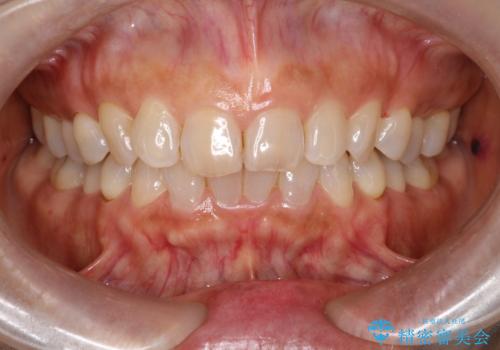

オフィスホワイトニング スペシャルコース

治療症例の内容

- 10年以上メンテナンスで通院されている方です。

初めては知覚過敏があり健康目的としてメンテナンスを希望されていましたが、最近は白いに興味が出てきたようで、歯の黄ばみ予防を兼ねてエアーフローをされる事もあります。

1回来院で白くしていくホワイトニングではなく、何回か受けて頂き、徐々に白くしていくコースとなります。知覚過敏が心配な方やホームホワイトニングをしながらの方にもおすすめです。